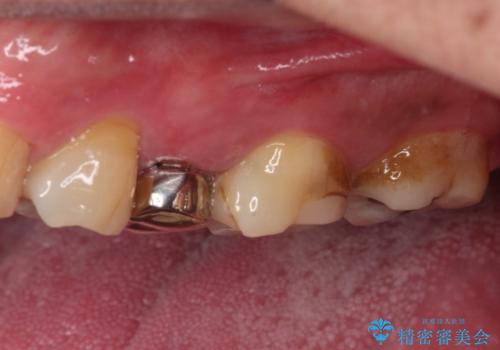

根管治療の際に、咬み合う上顎の銀歯が内側に入り込んでいることも気になるとのことであったため、部分矯正を行い、その後上下を同時に補綴治療することとしました。

部分矯正を行うと咬み合わせが定まらないことがありますが、今回は矯正治療後に上下補綴治療を行ったため、安定した咬み合わせにて仕上げることができました。